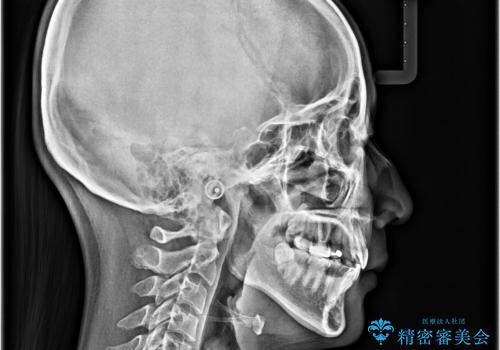

- 八重歯やクロスバイトを気にして来院された患者様です。

口元の突出感はありませんでしたが、デコボコが強く、非抜歯矯正とすると出っ歯仕上がりとなる可能性があったため、上下左右の第一小臼歯4本を抜歯し、ワイヤー装置にて矯正治療を行うこととしました。

デコボコがスッキリするだけでなく、口元の突出感も少し改善され、満足のいく仕上がりとなりました。